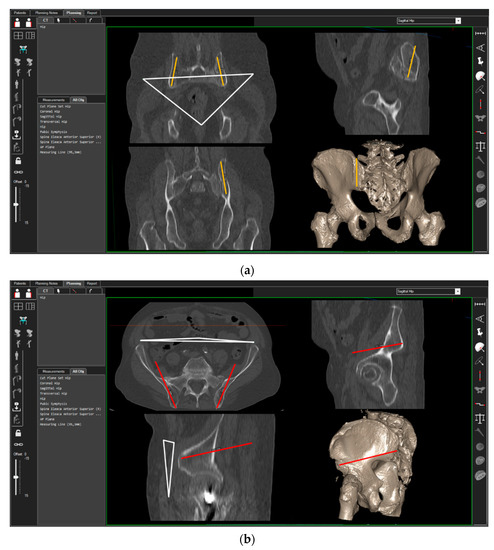

3D-CT scans of 40 randomly chosen patients (20 women, 20 men) were analyzed. CT measurements were carried out using the ‘semi-automatic’ function of a digital 3D‑CT-based planning software (Modicas, Erlangen, Germany). This software offers the possibility to assess the pelvis in three dimensions, to exactly determine the axes, and to automatically calculate angles and measure distances (Figure 2). First, the pelvis was virtually aligned in order to bring the anterior pelvic plane (APP) in congruence with the coronal plane in order to have a constant starting point. The APP is defined as the triangle between the pelvic symphysis and both anterior superior iliac spines (ASIS) [13] (Figure 2, please see the white triangle). In this context, fiducial landmarks from the frontal, sagittal, and axial view were identified and the specimens’ preoperative and postoperative position was carefully adjusted in order to exclude any rotational errors during the CT measurements.

The possible entry points for the iliac screws in the posterior iliac crest were identified. For the TIFI placed in cranio-caudal direction (TIFIcc), the entry point was chosen 1 cm lateral and 2 cm above the posterior superior iliac spine. The screw (Screw-TIFIcc) was oriented in the direction of the ischiadic notch parallel to the posterior gluteal line, as described previously [9]. For the alternative stabilization technique described by Schmitz et al. [10], the ileum screw was placed in a dorso-ventral direction (TIFIdv) and the entry point was chosen 1 cm above the posterior inferior iliac spine (PIIS). The screw (Screw-TIFIdv) was positioned in the direction of the anterior inferior iliac spine (AIIS).

Figure 2. Setting of the 3D-CT-based measurement of the ilium screws in cranio-caudal (a) and dorso-ventral (b) orientation. White triangle = anterior pelvic plane (APP); orange line = position of the TIFIcc, red line = position of the TIFIdv.